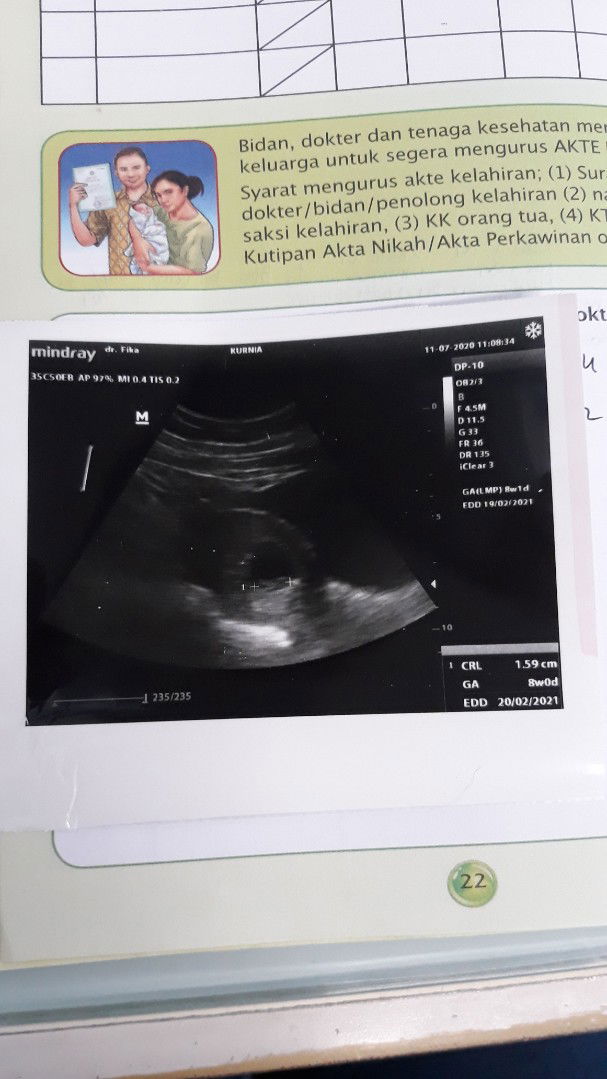

hamil 8 minggu

dokter memperkirakan sya hamil 8 minggu stelah d usg blm ada detak jantung dokter menyarankan sya kuret karna janin tidak ada detak jantung, gmn y mom? apakah ada janin lebih 8 minggu bru terdengar detak jantung?